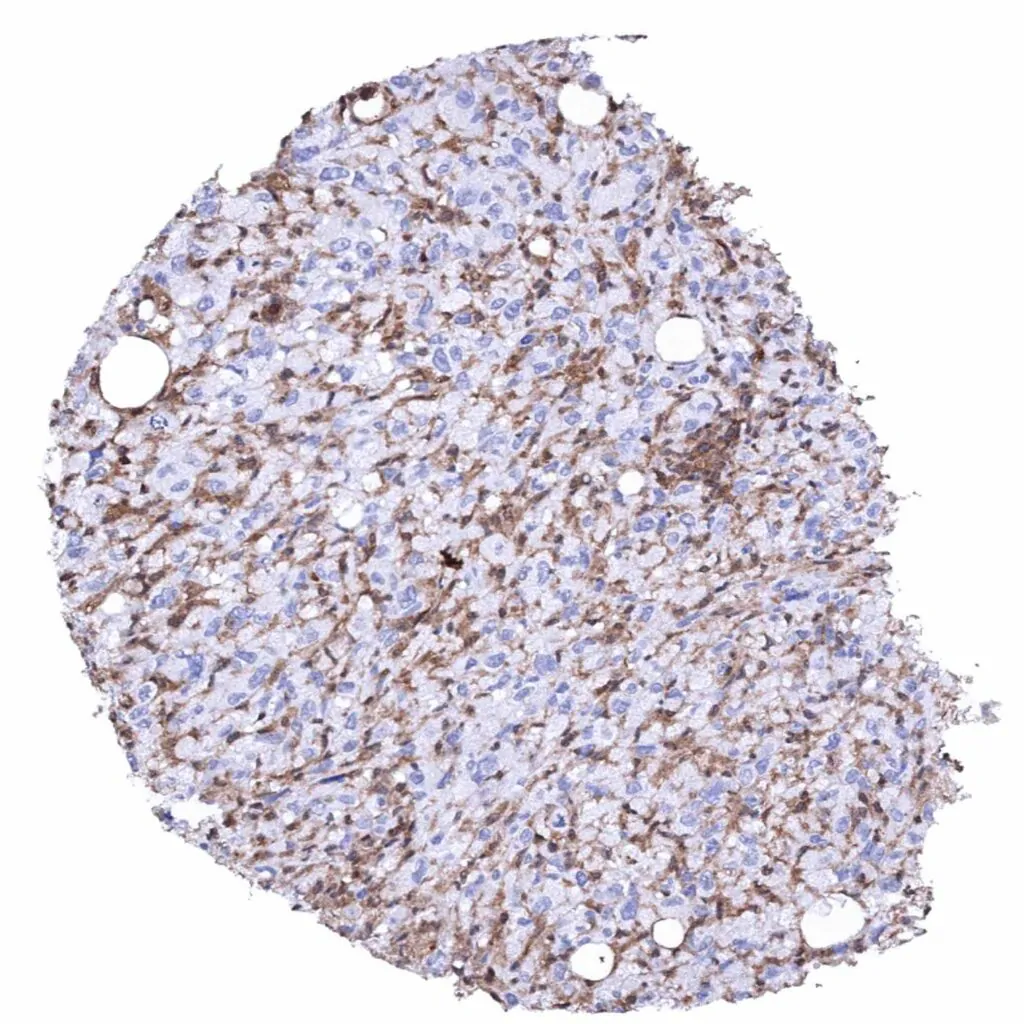

Lymph node – Hodgkin's lymphoma with complete absence of MTAP staining in tumor cells. Intense MTAP staining of associated non-neoplassic cells.

Lymph node – Hodgkin's lymphoma with complete absence of MTAP staining in tumor cells. Intense MTAP staining of associated non-neoplassic cells